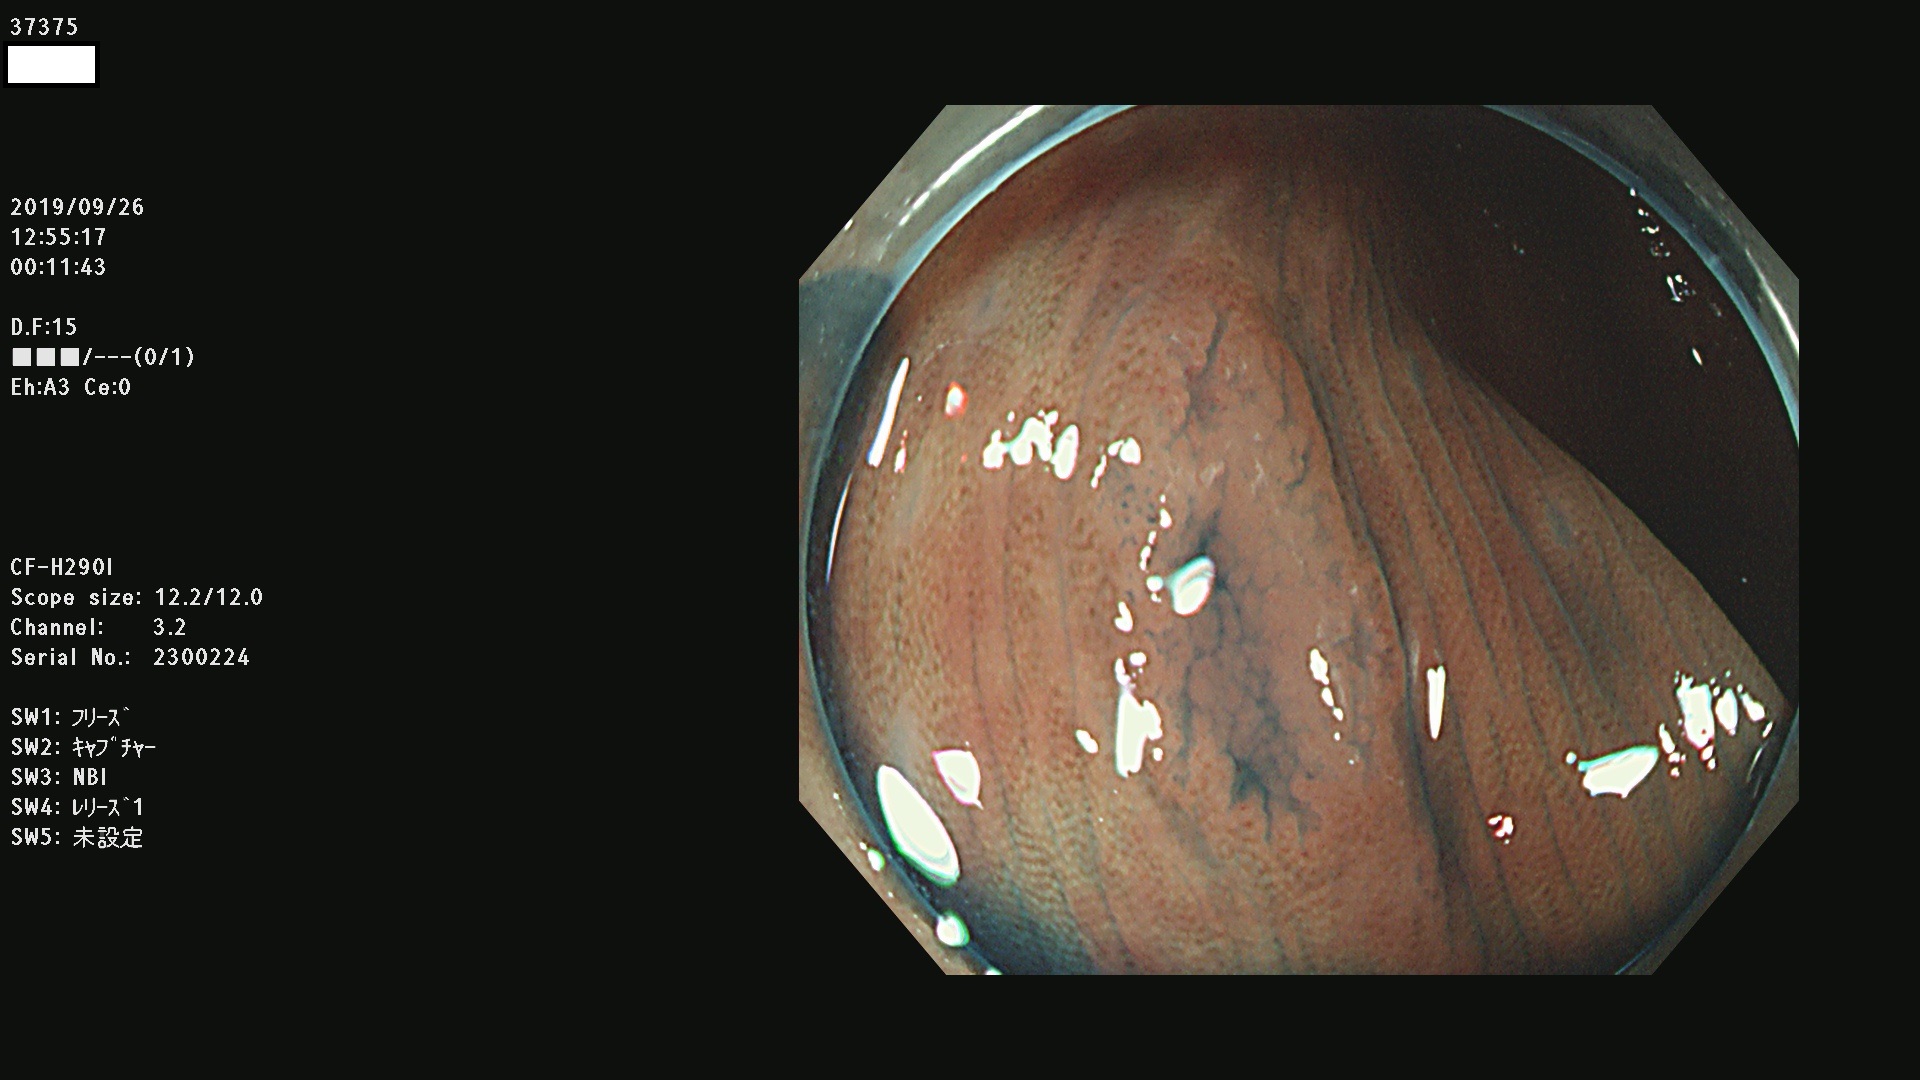

37300(SSAPのみ) 37301 37303 37304 37306 37307 37308 37309 37312 37313 37315(SSAPのみ) 37316 37317(SSAPのみ) 37319 37321(SSAPのみ) 37322 37323 37324 37325 37326 37328(SSAPのみ) 37329 37330 37331 37332(SSAPのみ) 37333 37334 37336 37337 37338 37340 37342 37343(SSAPのみ) 37344 37345 37346 37347 37348 37352(SSAPのみ) 37353 37354 37355 37356 37358 37360 37361(SSAPのみ) 37362 37363 37366 37367 37369 37370 37371 37372(SSAPのみ) 37375 37376 37377 37380 37381(SSAPのみ) 37382 37383 37384 37385(SSAPのみ) 37386 37387 37388 37389 37390 37392(SSAPのみ) 37393 37394 37395 37396(SSAPのみ) 37397 37398(SSAPのみ) 37399

発見困難で危険性の高い平坦型病変(上記100名より抽出) )